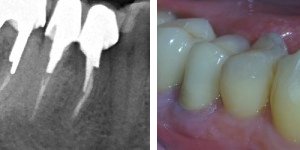

Poniżej zdjęcie rentgenowskie po zabiegu premolaryzacji. Widzimy już dwa oddzielne zęby.

Gojenie trwa około roku.

Jeśli zdjęcie rentgenowskie wykonane po roku pokazuje wygojoną kość a pacjent nie ma żadnych dolegliwośći, można przystąpić do odbudowy protetycznej.

Wykonuje się dwie mniejsze korony zamiast jednej, co umożliwia prawidłowe czyszczenie. Zęby wyglądają naturalnie i spełnieją swe funkcje.